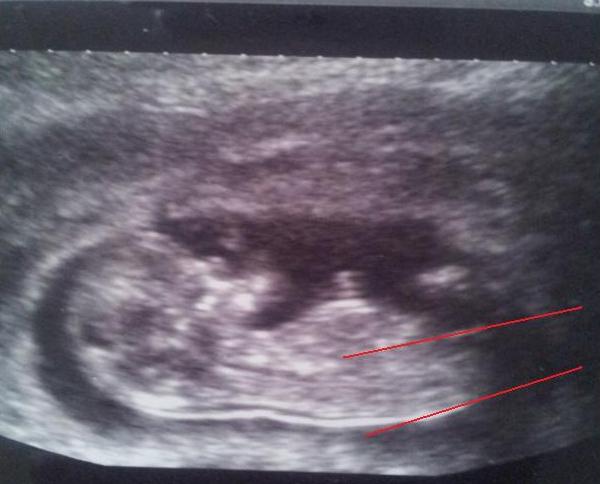

Would really appreciate your gender predictions based on my 12+3 scan?? Thanks

ive attempted to draw angles on ... Attachment 6304

I did the same on yours bc it was tricky but I had the spine angled a bit lower which is why I think I thought boy. I really can't exactly tell where to draw the line for the spine

My lines for your picture are a little different because of the spine......but it still looks like it could be a possible girl

My first thought was girl but I cannot tell if there is a bump on that nub or not. I would have expected much more of an angle at your gestation for it to be a boy but I do think the spine is curled just a bit!